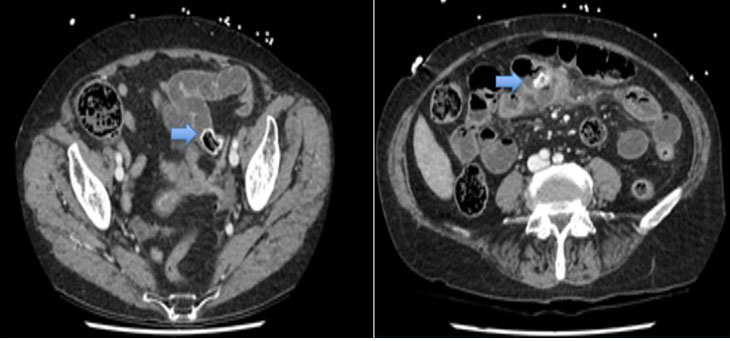

Operative findings

There was abundant blood in the gastric fundus (Figure 1); however, no discernible active bleeding was found in the esophagus (Figure 2), stomach, or first two parts of the duodenum. A medium-sized hiatus hernia measuring about 4 cm was noted (Figure 1) and on closer inspect a Cameron lesion was identified with overlying blood clot (Figure 3) in the hiatus hernia. Hemospray® endoscopic sealant (Cook Medical) was sprayed over the clot (Figure 4).

Figure 1: Retroflexion view demonstrating hiatus hernia and gastric fundus with pooled blood.